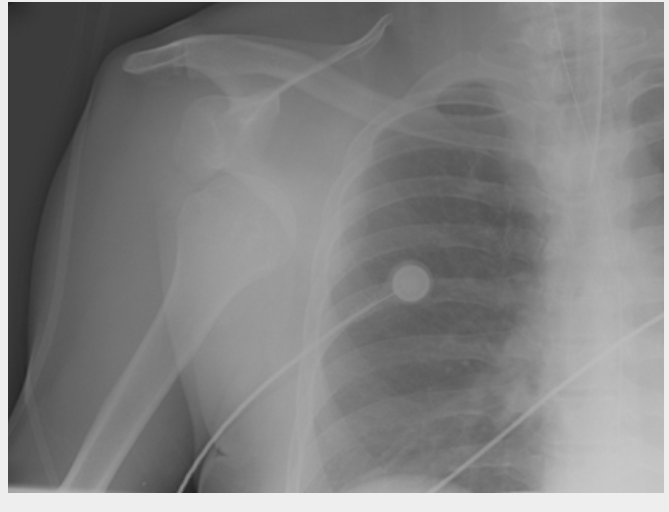

Anteroposterior x-ray view of a shoulder showing a missed posterior dislocation: the glenohumeral joint appears reduced